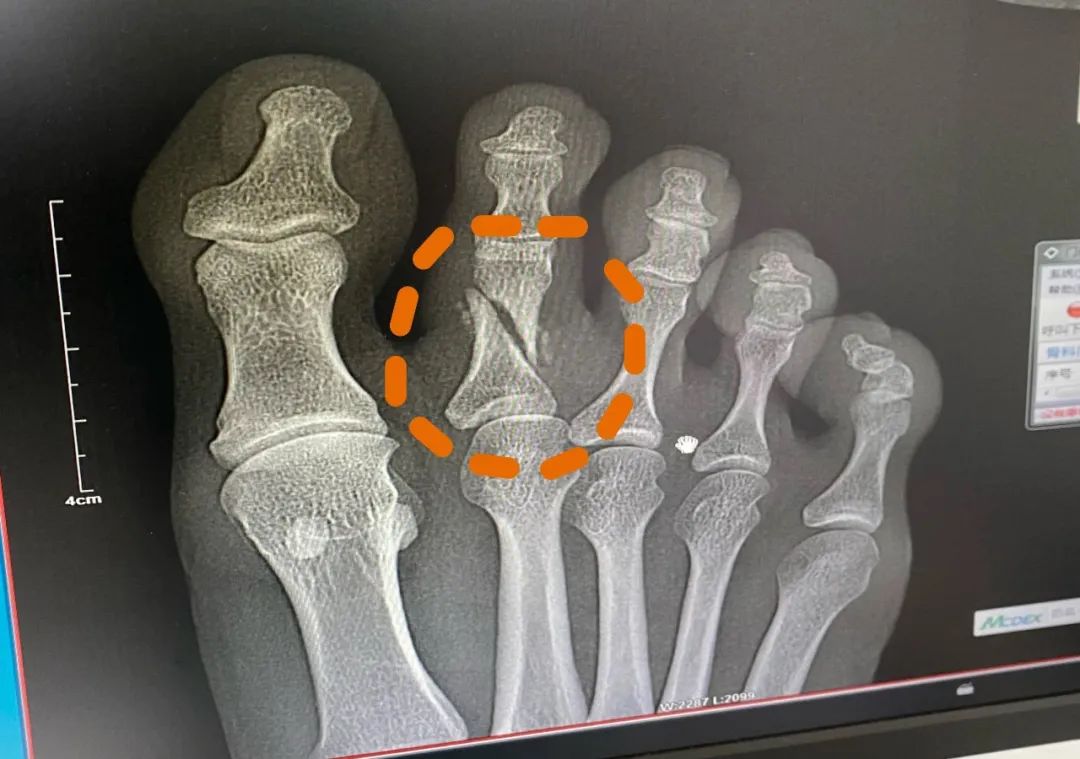

在此之前,她参加了由吴京和刘天池联合创办的动作与表演实战训练营,在这里经历过高强度的训练。第一期仅有14名学员,训练持续75天。训练时间长,强度大,同期有学员因骨裂被送医,曾霜旖也疼得厉害,却始终没向教练透露。“我怕他们让我休息,”她说,“那样的话,这两个月的训练就白费了。”在第一次参加马术集训前,她的右趾骨意外骨折,为了在高强度训练中保持专注,她没打石膏,第一次吃了止痛药坚持完十天训练。

曾霜旖趾骨骨折的片子